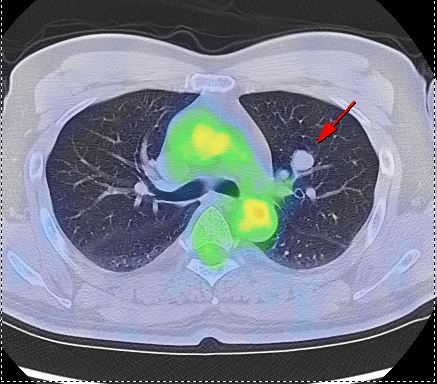

⑥CTやMRIなどと組み合わせるとより詳しくがんがわかります

CTやMRI検査は、体の中の組織や細胞の「かたち」を画像でとらえ、周囲臓器との関係をみることによってその異常を見つけます。これに対しPET検査は、細胞の「活動状態」を画像でとらえる検査法です。

PET検査を組み合わせることで、違った種類の情報が加わり、CTやMRIなどの検査だけでは見つかりにくかったがんが、発見しやすくなります。

またPETはCTやMRIに比較して空間分解能が低く異常が発見されても病気がどこにあるかはっきりわからない場合があります。そこでCTやMRIなどと合成(フュージョン)すると、病変部位の解剖学的な「形や大きさ」を正確に把握することができます。

▲早期右乳癌